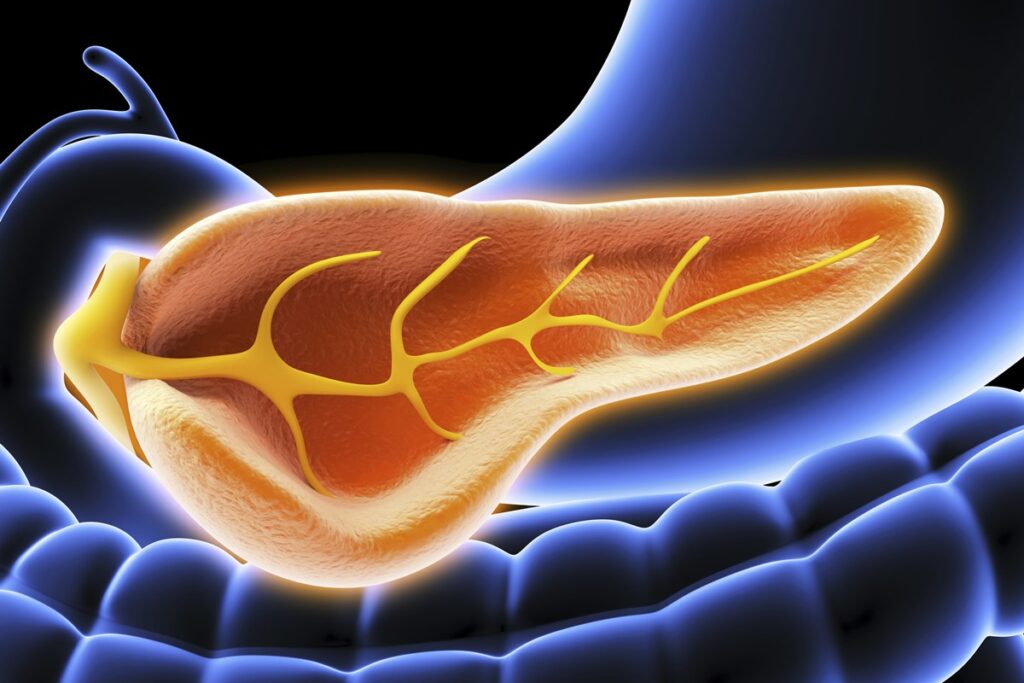

O pâncreas é responsável pela produções de insulina e pela absorção de enzimas digestivas

SEBASTIAN KAULITZKI/SCIENCE PHOTO LIBRARY/Getty Images 2 de 4